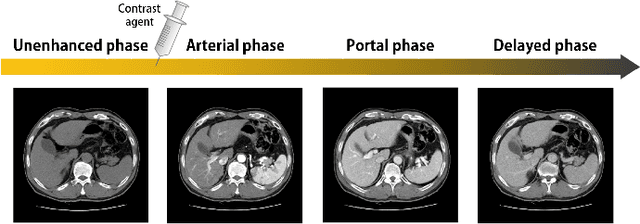

Image registration is a fundamental task in medical image analysis. Recently, deep learning based image registration methods have been extensively investigated due to their excellent performance despite the ultra-fast computational time. However, the existing deep learning methods still have limitation in the preservation of original topology during the deformation with registration vector fields. To address this issues, here we present a cycle-consistent deformable image registration. The cycle consistency enhances image registration performance by providing an implicit regularization to preserve topology during the deformation. The proposed method is so flexible that can be applied for both 2D and 3D registration problems for various applications, and can be easily extended to multi-scale implementation to deal with the memory issues in large volume registration. Experimental results on various datasets from medical and non-medical applications demonstrate that the proposed method provides effective and accurate registration on diverse image pairs within a few seconds. Qualitative and quantitative evaluations on deformation fields also verify the effectiveness of the cycle consistency of the proposed method.